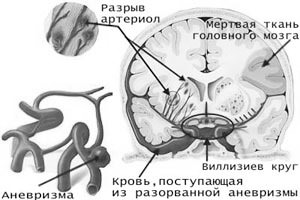

Головной мозг — острое нарушение мозгового кровообращения (инсульт)

Инсульт — следствие нарушения кровоснабжения участка головного мозга в результате тромбоза (закупорки) или разрыва сосуда. Самой частой причиной инсульта у курильщиков является тромбоз, так как курение приводит к сгущению крови и спонтанному формированию тромбов. Разрыв сосуда, влекущий за собой кровоизлияние в мозг – тоже не редкость, ведь под влиянием курения стенки церебральных сосудов истончаются и теряют свою эластичность.